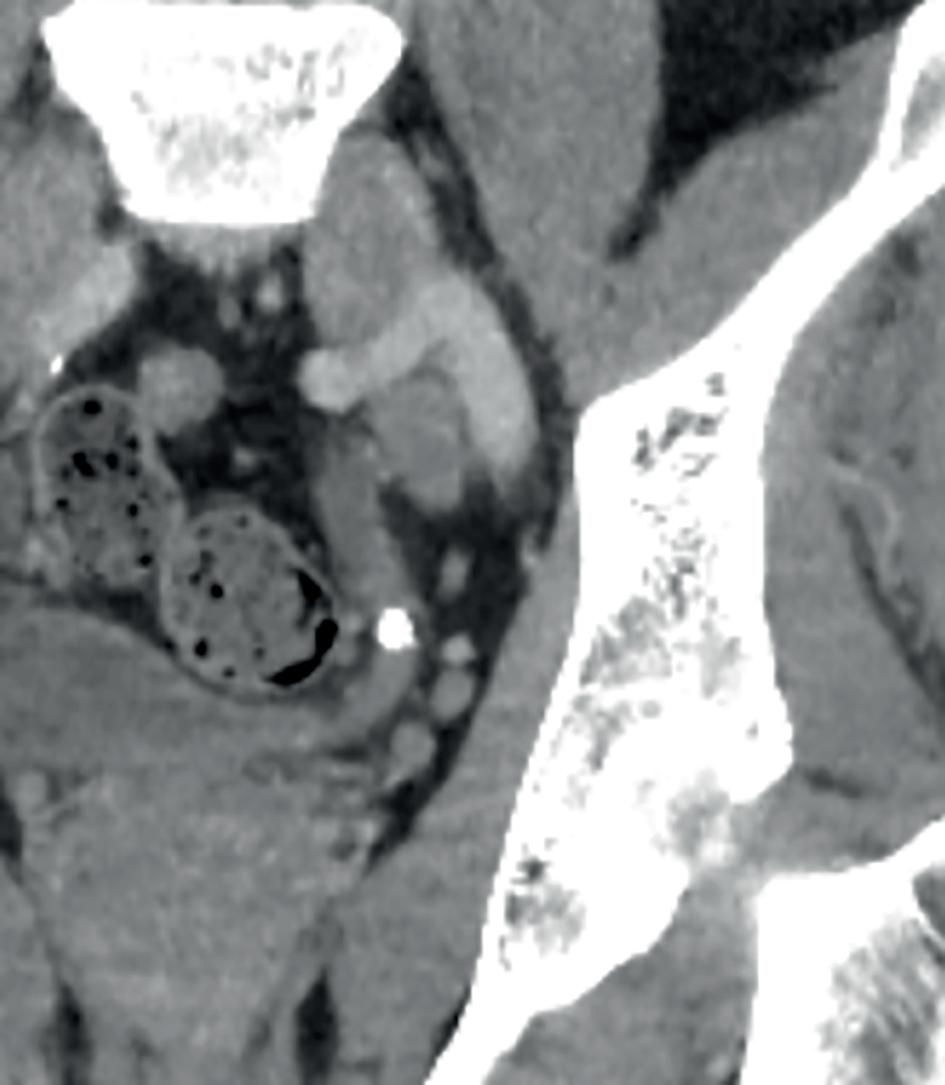

En spesiell pasient har fulgt meg gjennom flere av mine opphold i Nepal. Jeg traff ham første gang i 2018. Han hadde fått kvestet høyre ben av en stor stein omtrent ti år tidligere. Pasienten ble den gang sendt til Kathmandu for å få behandlet benet sitt. Med lappeplastikk på leggen, delhudstransplantasjoner og margnagling av femur fikk man reddet underekstremiteten, men dessverre satt han igjen med en osteomyelitt i høyre distale femur (Bilde 2). Han ble reoperert flere ganger i ettertid, men til ingen nytte. Det var vedvarende sekresjon av illeluktende puss (penicillin-sensitive Staphylococcus aureus) fra dorsalt på låret. Vi, ved sykehuset i Okhaldhunga, reviderte benet hans på nytt med en lokal sekvestrektomi (fjerning av dødt benvev - sekvester) og S53P4 bioaktive glass- implantasjon (4,5). Dessverre hjalp dette bare i noen måneder. Deretter var infeksjonen tilbake igjen. Om alkoholproblemet hans kom før eller etter ulykken vet jeg ikke, men det hjalp heller ikke med tanke på etterlevelse av instruksjonene han fikk.

behandling Pasienten innfant seg ikke med dette og oppsøkte derfor på nytt sykehuset i Okhaldhunga i 2022 for en ”second opinion”. Det var da jeg traff ham for andre gang. Vi fant at pasienten hadde to fistelganger, den ene secernerende, og på nytt et sekvester dorsalt i distale femur. Pasienten fikk beskjed om at vi ville gi ham en siste sjanse. Det kunne bli en stor operasjon under to betingelser: Han måtte ta antibiotika tablettene sine etter operasjonen og dersom det ble et problem i forløpet måtte vi få lov å amputere benet. Det sa han ja til. Noen dager senere var vi i gang med operasjonen – via lateral subvastus tilgang til dorsale distale femur ble det utført saucerisasjon (fjerning av kortikalt ben og sekundær bentilheling) av hele bakre distale femur sirkumferens, margboring mot proksimalt og kyrettasje, i tillegg til margboring mot distalt (6). Heldigvis hadde jeg med meg en meget flink nepali kirurg som gjorde en møysommelig eksisjon av begge fistelgangene (Bilde 3). Vi la bølgedren i sårhulene og gjorde primær lukking. Pasienten fikk postoperativt kloksacillin i.v. 2 g x 4 i to uker, deretter dikloksacillin 1 g x 4 i fire uker (7). Han ble også instruert i å avstå fra vektbæring på høyre ben i rundt seks måneder, samt at han måtte bruke en stabiliserende kneortose for å forhindre fraktur av en tydelig svekket rørknokkel.